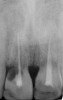

Figure 11   Initial view of resorbed maxillary central incisors.

Figure 11